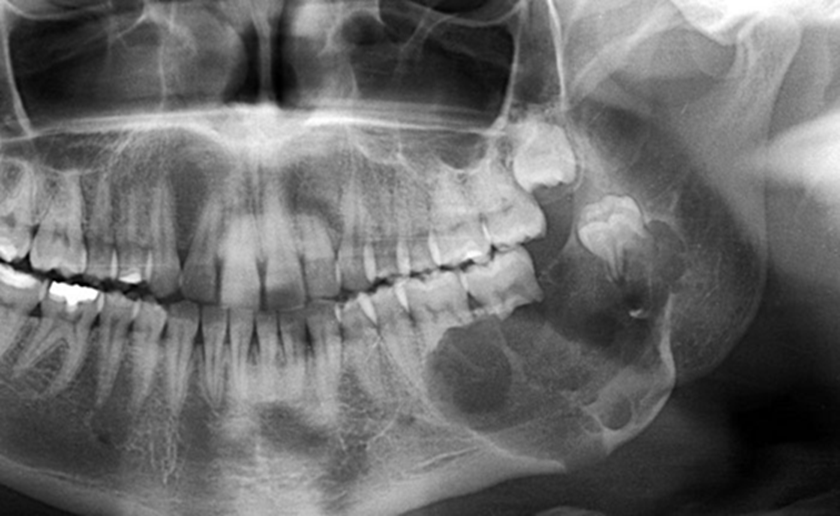

Hình ảnh của Kasim Hoàng Vũ khi mắc bệnh nặng, gương mặt biến dạng khó nhận ra

U xương hàm là tình trạng xuất hiện khối u phát triển bất thường trong xương hàm trên hoặc hàm dưới, có thể là u lành tính hoặc ác tính. Bệnh không phổ biến như sâu răng hay viêm nha chu nhưng lại âm thầm và dễ bị bỏ qua vì triệu chứng ban đầu khá mờ nhạt. Nguyên nhân gây u xương hàm rất đa dạng. Một số trường hợp liên quan đến rối loạn phát triển mô răng, u nguyên bào men, u xương lành tính. Trường hợp ác tính có thể là ung thư xương nguyên phát hoặc ung thư từ cơ quan khác di căn đến xương hàm. Ngoài ra, tiền sử viêm nhiễm răng miệng kéo dài, chấn thương vùng hàm mặt, tiếp xúc tia xạ, yếu tố di truyền hoặc đột biến gen cũng được xem là yếu tố nguy cơ.

Tác động của u xương hàm lên sức khỏe không chỉ dừng ở vấn đề thẩm mỹ. Khi khối u phát triển, người bệnh có thể thấy sưng nề vùng má hoặc lợi, đau âm ỉ, tê môi cằm, răng lung lay không rõ nguyên nhân, khó nhai hoặc há miệng hạn chế. Nếu là u ác tính, khối u có xu hướng xâm lấn nhanh, phá hủy cấu trúc xương, lan vào xoang hàm, hốc mắt hoặc nền sọ. Điều này có thể gây biến dạng khuôn mặt, suy giảm chức năng ăn nhai, nói chuyện và ảnh hưởng nghiêm trọng đến tâm lý người bệnh.